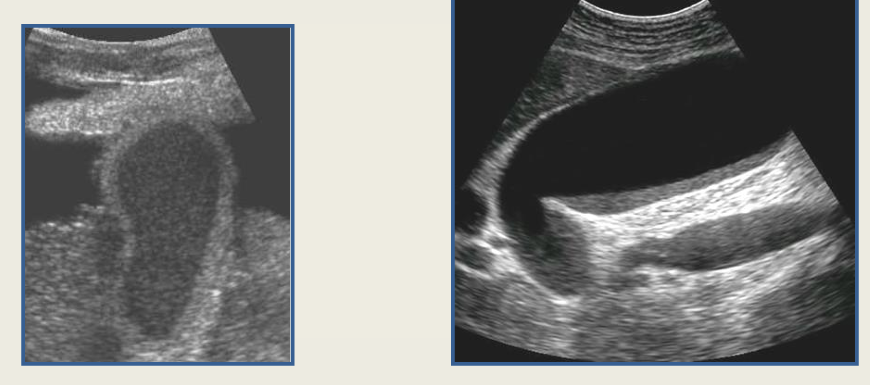

term image

sludge

porcelain GB

gb polyps